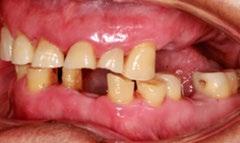

Figura 1. Fotografías clínicas intraorales oclusales, perfil derecho, frontales iniciales y radiografía panorámica en las que se observa caries, extrusión de piezas y ensanchamiento del ligamento periodontal.

Se reporta el caso de un paciente masculino de 74 años, con antecedentes de extracciones por caries, que acude a consulta por incomodidad al comer. Fue remitido al Centro Educativo Multidisciplinario de Rehabilitación Oral, Tarímbaro, Michoacán, en octubre de 2022. Al examen clínico se encontró cálculo dental generalizado, gingivitis localizada, movilidad dental, atrición en el sector anterosuperior e inferior, ausencia de piezas posteroinferiores y superiores, y alteración de la DVO. El análisis de fotografías clínicas intraorales mostró extrusión de raíces de piezas antagonistas en las zonas edéntulas,

oclusión borde a borde y retracción gingival (Figura 1). En los estudios imagenológicos se observó ensanchamiento del ligamento periodontal y caries (Figura 2).